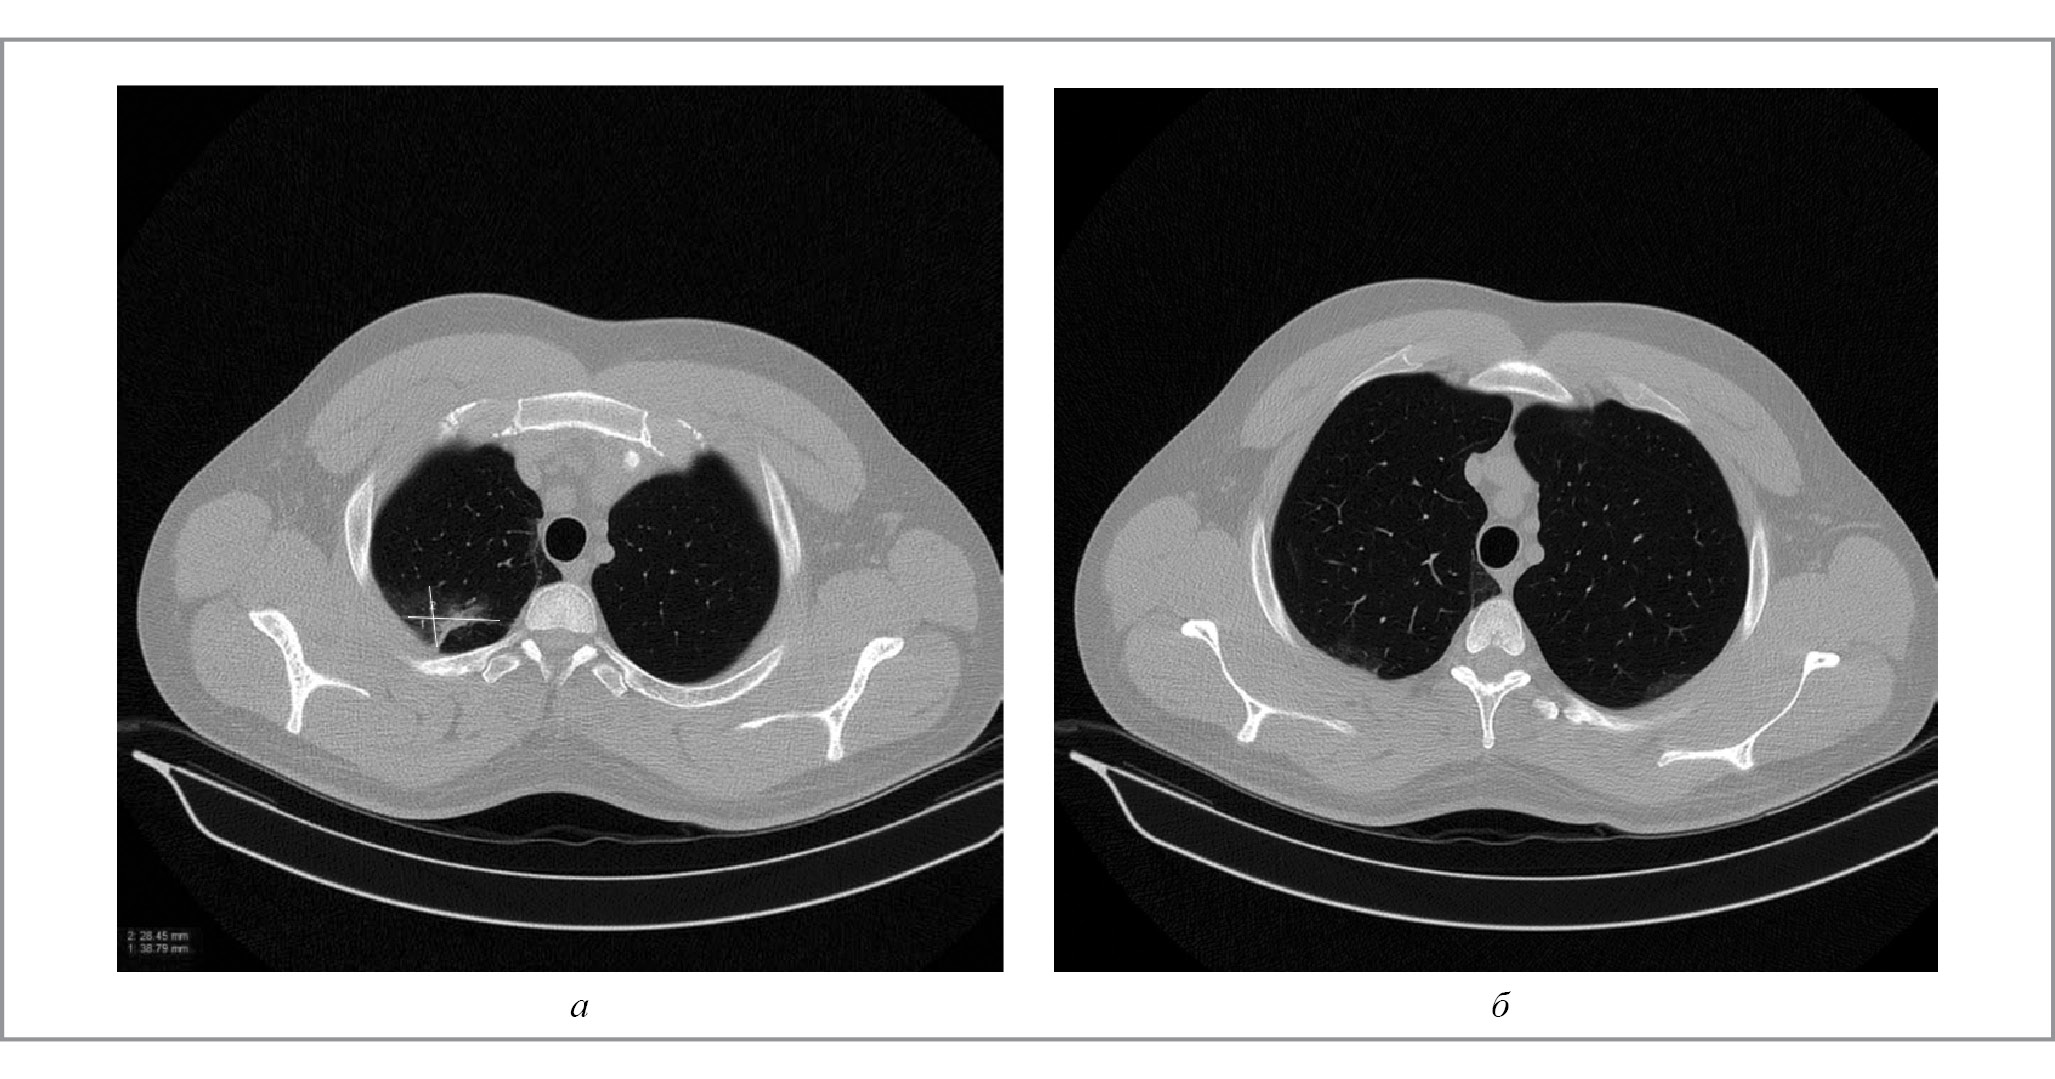

Данная тактика привела к существенному и быстрому улучшению рентгенологической картины в легких. Результаты контрольной МСКТ через 7 дней после отмены месалазина демонстрировали выраженную положительную динамику в виде уменьшения инфильтрации легочной ткани, явления консолидации приобрели вид «матовости» (рис. 2). При анализе данных МСКТ через 1,5 мес после отмены препарата отмечались положительная динамика в виде тотального регресса инфильтративных изменений в легких, а также нормализация воспалительных маркеров крови, но сохранялся легкий тромбоцитоз (424×109/л), вероятно, из-за активности ЯК.

Рис. 2. Результаты МСКТ органов грудной клетки пациента С. Через 7 дней после отмены месалазина: а – срез 887 мм; б – 902 мм.